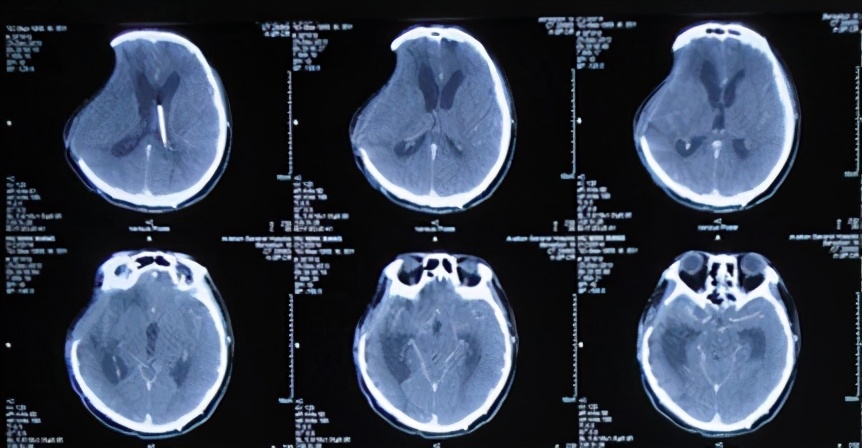

2013年11月21日即抗感染23天后即入院术后第51天(开颅术后第67天),给予试夹闭引流管观察骨窗情况。但在夹毕引流管次日患者出现右侧骨窗膨隆伴嗜睡,复查头CT:脑室系统扩张明显(图-16),再次给予开放脑脊液引流管。

图-16:2013年11月22日头CT

2013年12月17日即继续脑脊液引流25天后即入院术后第77天(开颅术后第93天),进行了侧脑室腹腔分流术,分流术后第1天2013年12月18日术后情况稳定(图-17)。

术后患者恢复良好,但仍间断头痛发作,在2013年12月25日即分流术后第8天(开颅术后第101天),复查头CT:脑室无异常(图-18)。

图-18:2013年12月25日头CT